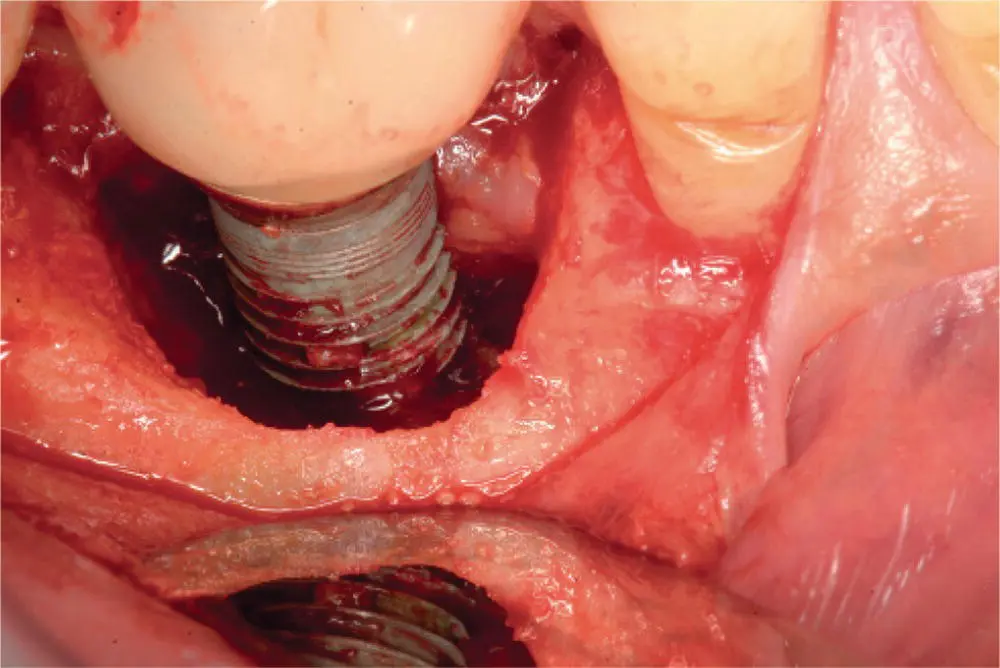

The phenomenon of peri‐implantitis is a well‐recognized and frustrating clinical problem for dental implant surgeons and patients. Part of this frustration lies in the fact that unlike periodontal disease, which is well defined and organized into categories, peri‐implantitis remains a rather ambiguous and debated term with variable clinical presentation. Some surgeons prefer the term “peri‐implantosis” since there are instances where there is bone loss surrounding an implant, but an absence of inflammation, so the term “peri‐implantitis” would not technically apply [35]. Most surgeons agree that for a diagnosis of peri‐implantitis to exist the presence of gingival recession and implant exposure and bone loss should be present. The distinguishing factor between peri‐implantitis and peri‐implant mucositis is that peri‐implantitis has bone loss around the implant ( Figure 3.16), while peri‐implant mucositis does not exhibit bone loss since the inflammation is confined to the mucosa ( Table 3.5). The bone loss in peri‐implantitis has been referred to as a “saucer‐shaped” bone defect around the implant on clinical examination and a peri‐implant radiolucency on radiographic imaging ( Figure 3.17). Peri‐implantitis often presents itself years after initial dental implant placement, and for this reason is included in the late‐stage infection category. Often, the peri‐implant bone loss is discovered incidentally on routine dental radiographs, and in the posterior region of the jaws, the presence of gingival inflammation, pain, BOP, purulence, and recession may go unrecognized by the patient for some time. Peri‐implantitis is believed to be due to biofilm formation on the implant surface with colonization by Staphylococcus aureus , which is an organism not typically seen with periodontitis. Risk factors include a history of periodontitis, smoking, poor oral hygiene, exposed implant threads, exposed surface coatings, and deep pocket depths. Treatment includes mechanical debridement with ultrasonic scalers or a titanium wire brush or the use of an erbium–YAG laser, implant surface decontamination with citric acid solution (5%), chlorhexidine irrigation, local antibiotics (25% tetracycline gel or fibers), systemic antibiotics (ornidazole or metronidazole), and improved oral hygiene that may be improved with an alteration in the prosthetic design (e.g., ridge‐lap prosthesis, or splinted prosthesis). Also, surgical reconstruction may include regenerative surgery with bone grafting, GBR, or connective tissue grafting, or resective surgery with osteoplasty and apically repositioned flaps. If there is retained cement in the area, it should be debrided. Of the options of debridement, resection, grafting, and GBR, bone grafting and GBR may have improved bone fill and pocket depth reduction in cases of peri‐implantitis.

A clear distinction needs to be made between increased probing depths around a dental implant and an established diagnosis of peri‐implantitis. Often bone levels around the implant may be ideal; however, a soft tissue pannus formation, in the form of a gingival pseudo‐pocket, may lead inexperienced clinicians to diagnosis a case of peri‐implantitis [36]. Although this excessive pseudo‐pocket is not ideal and can lead to oral hygiene issues with eventual bone loss, this is not an inevitable consequence. With meticulous oral hygiene maintenance and close follow‐up, this region can often be maintained without any untoward effects. In certain circumstances, gingivectomy may be required for excessive soft tissue, but careful attention must be paid to not affect the esthetic outcomes of the soft tissues, especially in the anterior esthetic zone. Once a diagnosis of peri‐implantitis has been established, the clinician must control the contributing factors, assess the presence of keratinized tissue, and evaluate the implant surface, implant location, restorative issues, and the presence of parafunctional habits [37]. Since these factors have been discussed previously, the discussion will focus on the surgical management of the implant with localized bone loss and inflammation with the understanding that other contributing factors have been addressed in order to optimize the outcome. Many of the initial stages of peri‐implantitis can be managed similar to periodontal disease. Nonsurgical peri‐implant debridement includes chemical and mechanical debridement. Chemical debridement with various topical agents such as chlorhexidine, citric acid, hydrogen peroxide, and tetracycline can be used. Mechanical debridement with implant scalers, titanium brushes, and lasers can be used. These techniques should be combined with patient education on the use of meticulous oral hygiene to help decrease peri‐implant soft tissue inflammation allowing for increased tissue adherence (soft tissue seal) around the implant fixture [38]. This increased tissue tone decreases bacterial migration along the implant surface and can prevent further infection and bone loss. More advanced cases of peri‐implantitis, with up to 50% bone loss, must be assessed regarding a guarded long‐term implant prognosis. If the implant is deemed salvageable, this will require open surgical debridement, bone grafting with guided tissue membrane regeneration, and temporary removal of the existing restoration [39]. Once appropriate bone and soft tissue healing has occurred, with evidence of adequate osseous regeneration around the implant, the implant may be uncovered and prosthetically restored. Peri‐implantitis that has progressed to greater than 50% bone loss, implant mobility, and recurring infections often necessitate implant removal and bone grafting with delayed implant replacement and restoration ( Algorithm 3.7).

Algorithm 3.7: Peri‐implantitis